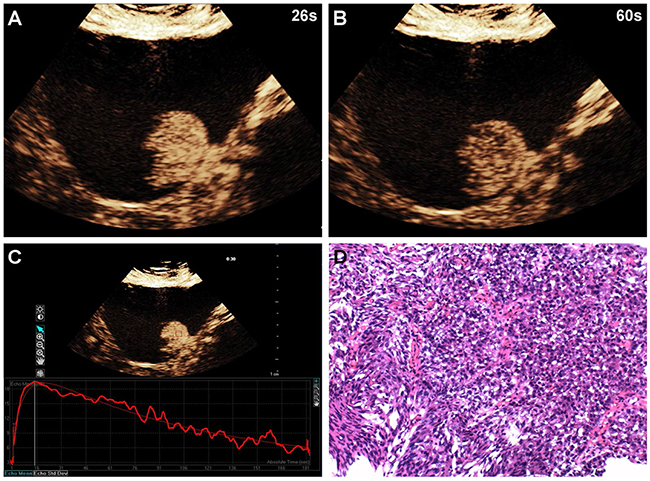

Of the 96 histopathological lesions, 54 were cases of high-grade urothelial carcinoma (4 Ta, 44 T1, 6 T2) and 42 were low-grade urothelial carcinomas (40 Ta, 2 T1) (Table 1). CEUS patterns were divided into three types: type I, fast wash-in and fast wash-out, 86% (36/42) of low-grade urothelial carcinomas showed quick enhancement in and around the lesions, and regression occurred earlier than in adjacent normal bladder wall (Figure 1); type II, slow wash-in and fast wash-out, 7% (4/54) of high-grade tumors and 5% (2/42) of low-grade tumors showed slow enhancement, and regression occurred earlier than in adjacent normal bladder wall; and type III, fast wash-in and slow wash-out, 85% (46/54) of high-grade urothelial carcinomas were quickly enhanced from the central tumor to its periphery, and regression occurred later than in adjacent normal bladder wall (Figure 2). Comparisons of all parameters of the gamma variate are shown in Table 2. There were no differences in AT and TTP between high- and low-grade bladder tumors (P>0.05). High-grade tumor PIs were greater compared to low-grade tumors, and low-grade tumor WTs were less than those of high-grade tumors (P<0.05). Combined enhancement patterns for high- versus low-grade bladder tumors are shown in Table 1.

Figure 2: A 58-year-old man with high-grade bladder cancer on the posterior bladder wall. CEUS shows strong and homogeneous lesion enhancement during the late arterial phase (26 sec) (A) and slow wash-out during the venous phase (60 sec) (B). Time-intensity curve shows fast wash-in and slow wash-out, and higher PI (C). Surgical specimen confirming high-grade bladder cancer (hematoxylin & eosin staining, original magnification ×100) (D).